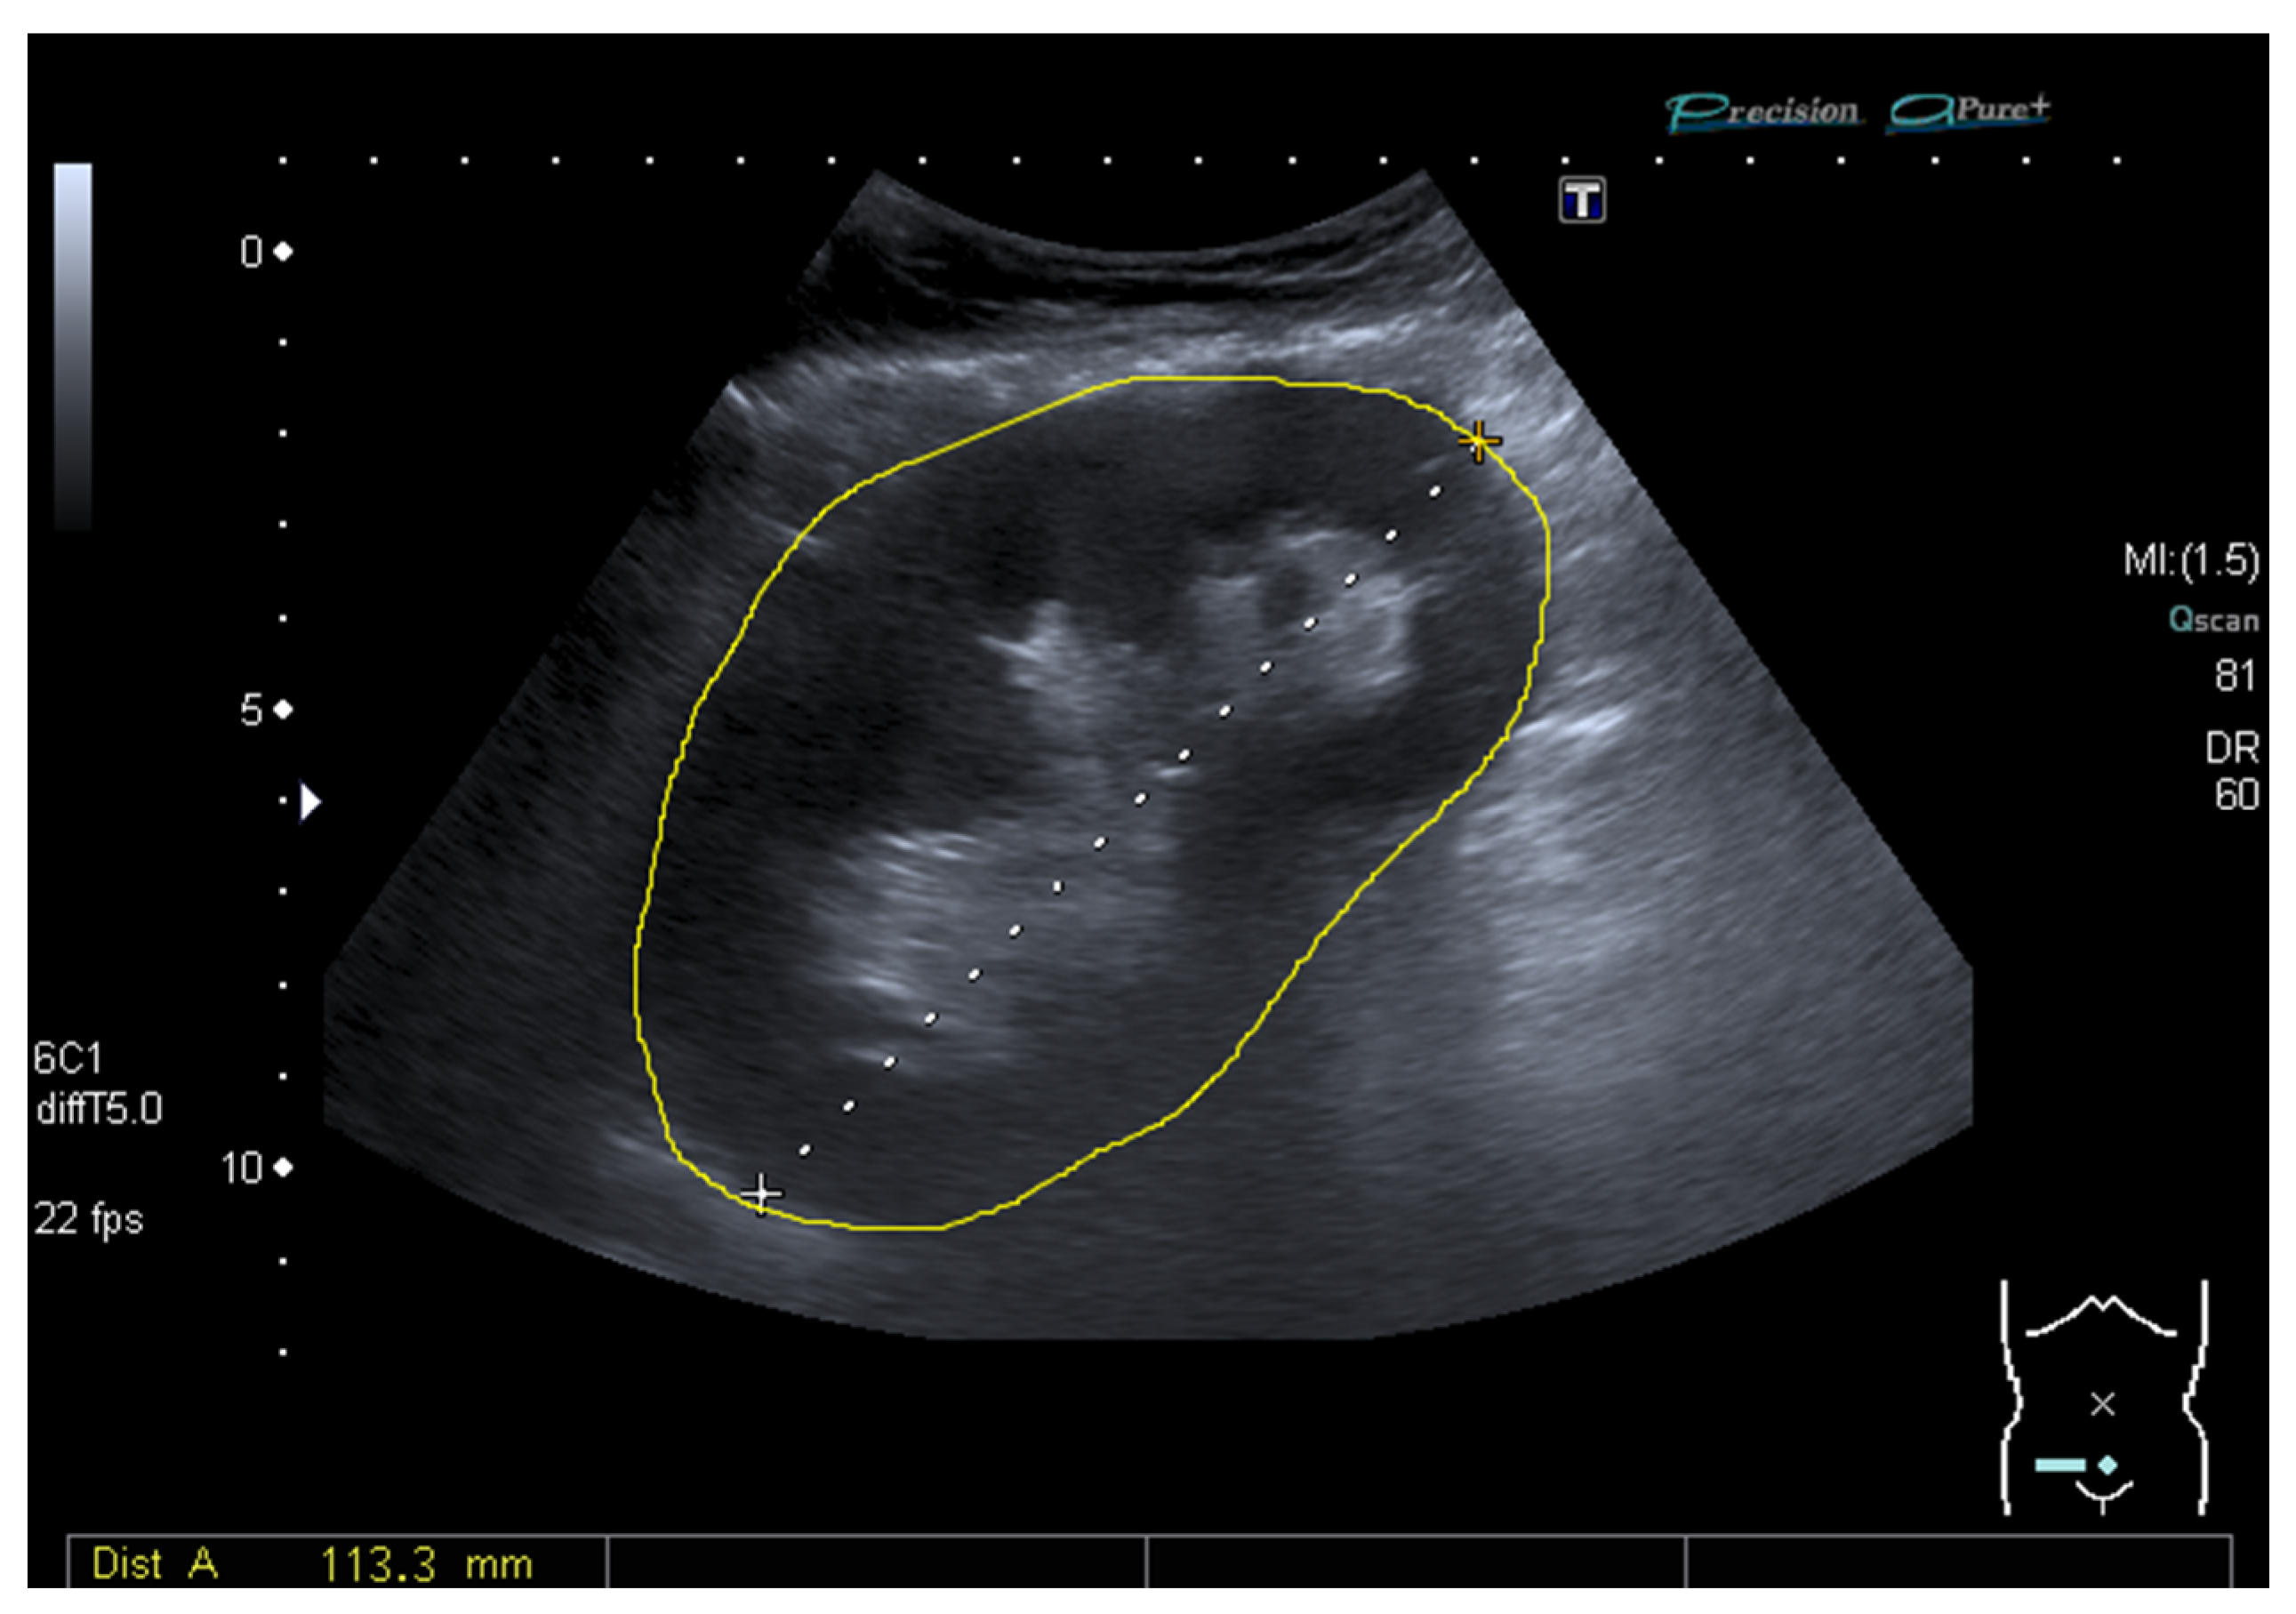

2.3. Ultrasound and Measurement of the Grayscale Median